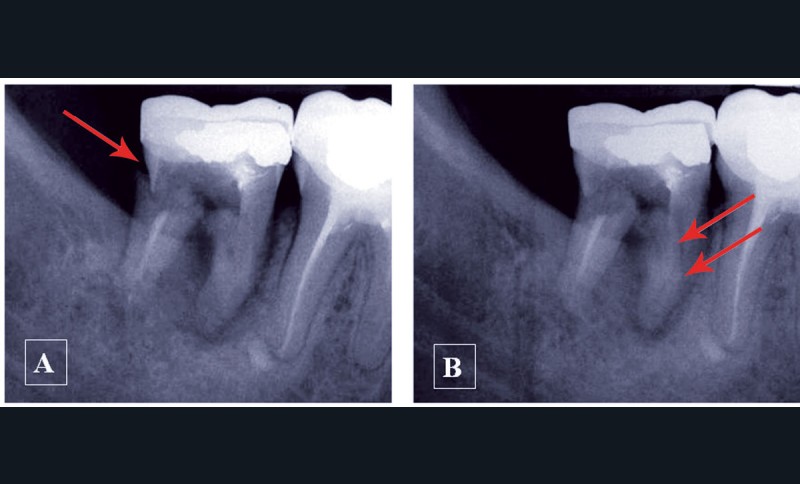

Une structure anatomique n’est radiologiquement visible que si le rayon directeur (axe du faisceau Rx incident) est tangent à cette structure. Une fracture radiculaire longitudinale ne sera mise en évidence qu’aux conditions d’une orientation favorable et de dimensions suffisantes (fig. 2).